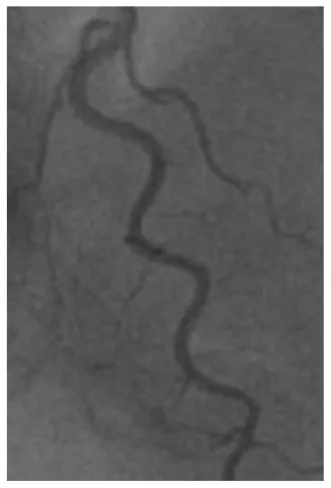

Since physiologic measurements during CFT were performed in the LAD artery, we also evaluated coronary tortuosity in the LAD artery. For the measurement of tortuosity, the left anterior oblique (LAO) 45-cranial 30° and the right anterior oblique (RAO) 30-cranial 30° views were used. The view after nitroglycerin infusion was primarily used, which was usually the LAO 45-cranial 30° view. Measurements of the other views were applied to estimate the angles of curvatures that were not entirely visualized on the LAO view. Measurements were performed at end-diastole as visualized in Figure 1. To quantify the severity of coronary tortuosity, the classification set up by Eleid et al. (7) was used. Mild tortuosity was defined as the presence of ≥3 consecutive curvatures of 45– 90° in the LAD artery or ≥3 consecutive curvatures of 90–180° in a diagonal of the LAD artery. Moderate tortuosity was defined as the presence of ≥3 consecutive curvatures of 90–180° in the LAD artery, and severe tortuosity was defined as the presence of ≥2 consecutive curvatures of ≥180° in the LAD artery. Patients who did not meet any of these criteria were defined as no tortuosity. The LAD artery were also examined on several additional markers of tortuosity (Table 1), including the S-curve sign, the intravessel symmetry sign, and the corkscrew sign, as described in the study by Ciurică et al. (16) Additionally, we considered the number of curvatures in the LAD artery as another marker of tortuosity (Figure 2).

Figure 1

Example of a tortuosity measurement of the left anterior descending artery. The blue marked angle defines the angle of the curvature surrounded by blue lines.

Example of a tortuosity assessment of the left anterior descending artery. The angles of all colored curvatures were measured to assess tortuosity: 1Blue curvature = 100°, 2Black curvature = 125°, 3Red curvature = 150°. In this case there was moderate tortuosity.